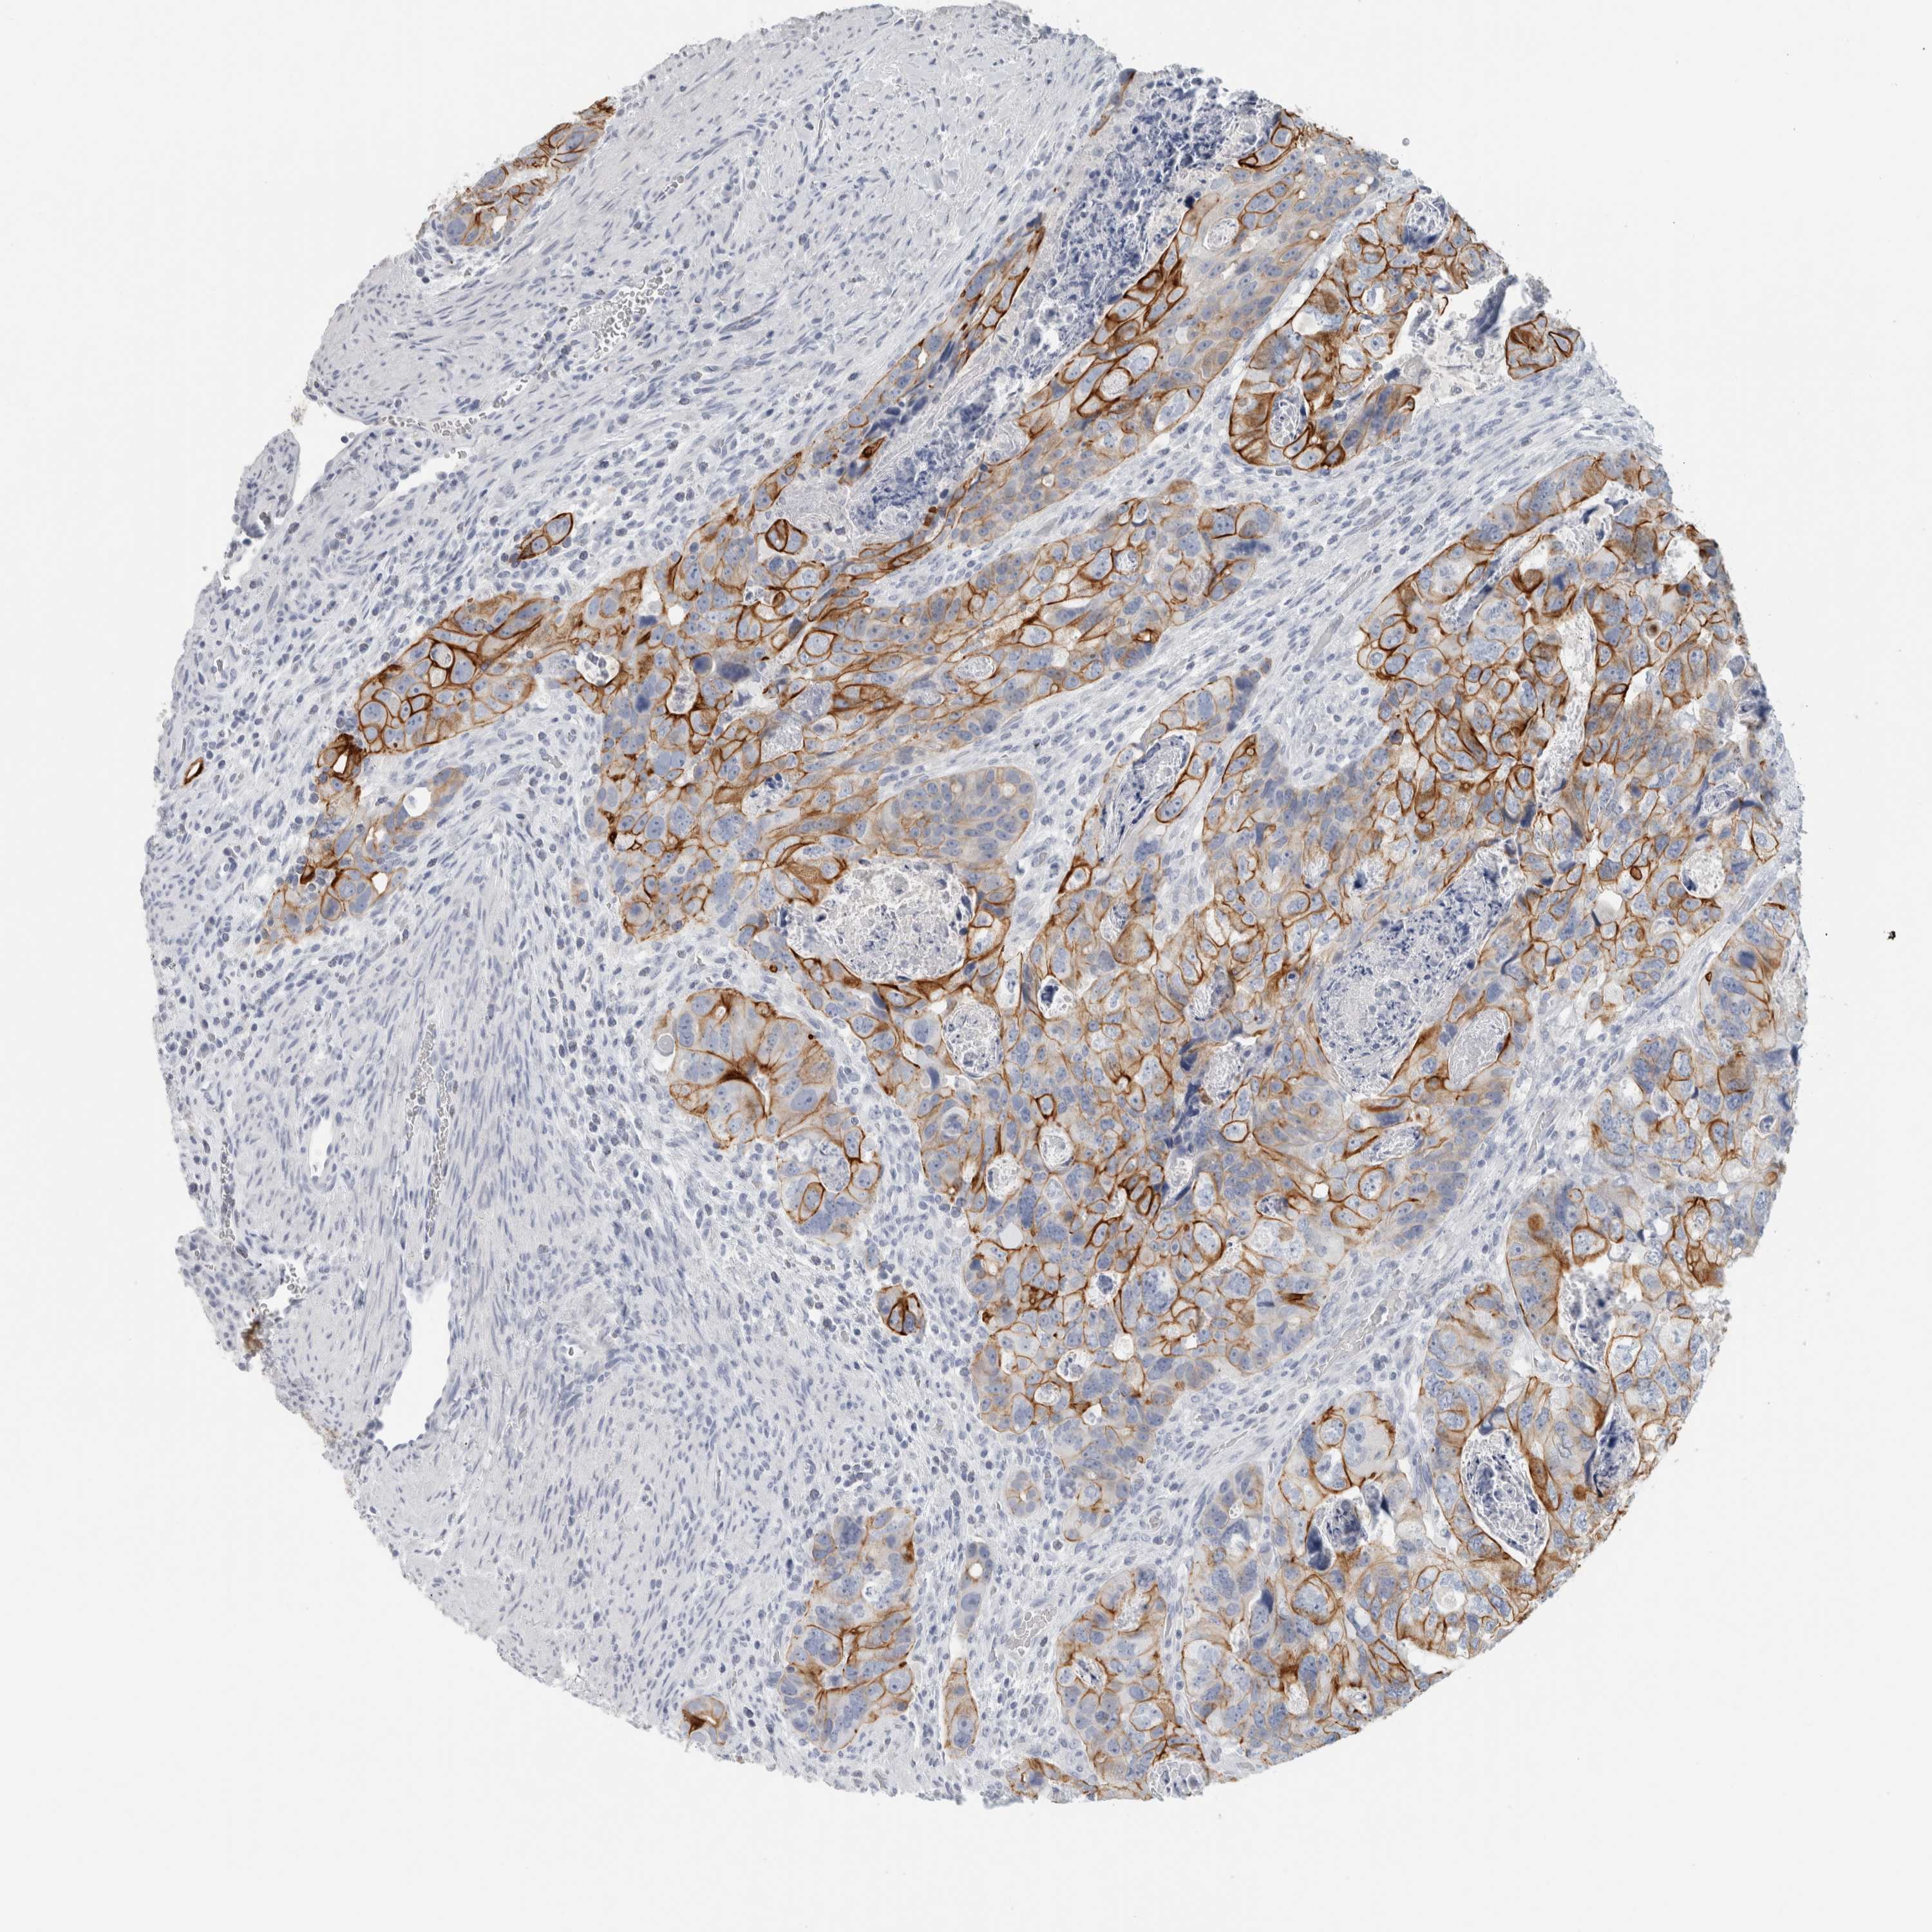

CANCER COLORECTAL CANCER Show tissue menu

Colorectal cancer

Human cancer

Colon adenocarcinoma